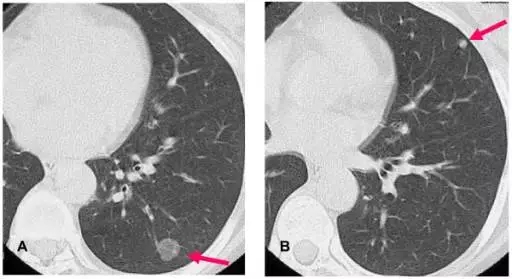

美国癌症学会2017年制定的《肺癌筛查指南》提出,年龄在55-77岁人群中,现在或曾经有每天一包有30年吸烟史或更多的人群,或在过去的15年内有连续吸烟或已经戒烟的人群,每年需要做胸部低剂量CT(LDCT)筛查检查。低剂量CT(LDCT)检查,目前是肺癌筛查的金标准。

图片来自Internet

一次肺部CT扫描产生200-300张片子,一个放射科医生全神贯注检查30个人的CT片子,需要150-180分钟。一家三甲医院平均每天接待200例左右的肺结节筛查患者,放射科医生每天至少需要读片4万张。这可以说是一种“劳役”般的工作,稍有疏忽,就会影响到诊断的准确率。

图片来自Internet

人工智能技术在医疗领域的应用,将极大地提高诊断的“准确率”,中国在肺癌诊断领域走在了世界前列,其突出优势表现在准确率达到90%以上,读片效率比人工读片提高5倍以上,基本上一分钟可以阅读一个病人的CT片。迅速读片出报告,可以大大减轻放射科医生读片劳苦,并且可以节省胶片等耗材的使用费用,如果广泛使用,可以缩小大小医院诊断水平的差距,让三、四线城市和乡村的病人享受到大医院的诊断水平。